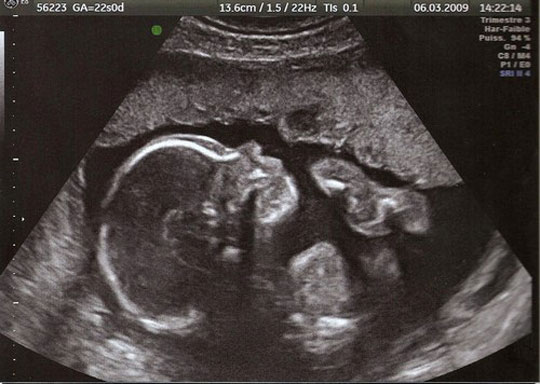

Les grandes avancées de la médecine

Ce diaporama permet de retracer une partie de l’histoire de la médecine à travers ses grandes avancées techniques ou ses découvertes. De l’invention du stéthoscope à l’arrivée de l’IRM, une vingtaine d’images accompagnées d’informations viendront en support pour alimenter une discussion autour de la vision de chacun sur ces progrès médicaux qui ont changé notre quotidien. N'oubliez pas de "dezipper" le diaporama avant de le lancer.